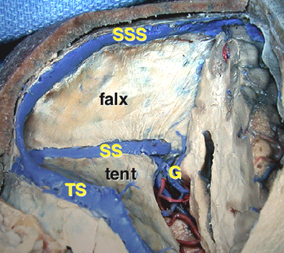

松果体周囲の静脈洞

Overview of the pineal region through the right occipital area. The occipital lobes, the falx, the tentorium, and the arachnoid membranes have been removed. BV = basal vein of Rosenthal, CV = cerebellar vermis, G = great vein of Galen, ICV = internal cerebral vein, MOV = medial occipital vein, P = pulvinar, PV = pericallosal vein, Q = quadrigeminal plate, S = splenium, SS = straight sinus, TS = transverse sinus